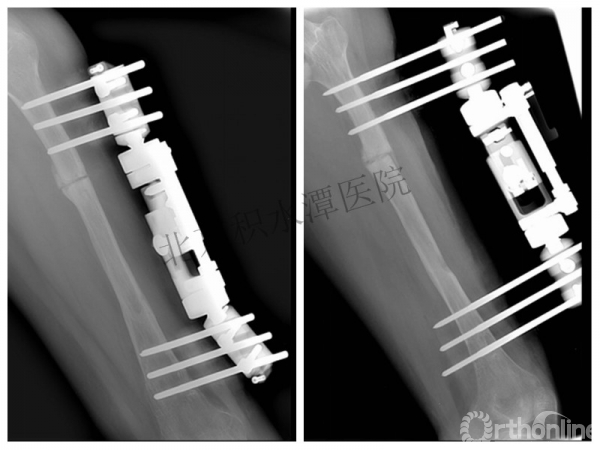

病例分享一

男孩 、5岁,初次骨折于2007年7月。

术后2年→再骨折→再次手术

钢板固定后一年

取板后再骨折→TEN

TEN取出后2个月

闭合复位再固定加尾帽

又过了4年!时间来到2015年

一年以后顺利愈合,实则危机四伏

数月后再骨折!牵引!

髋人字支具

外固定架术后一年

整整11年!是否治疗终结?

病人的付出?医生当反思!